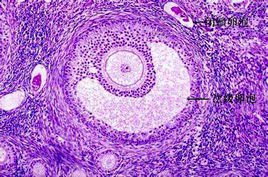

卵泡 维基百科 自由的百科全书